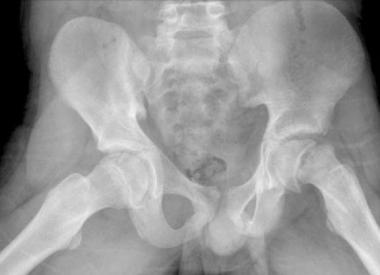

This 60kg 8 year old with left hip pain is hopping for an extra scoop?

Left Slipped Capital Femoral Epiphysis (SCFE)

If you can't describe this fracture to your Bone Bro, you're an outdated Stryker part?

Right intertrochanteric fracture